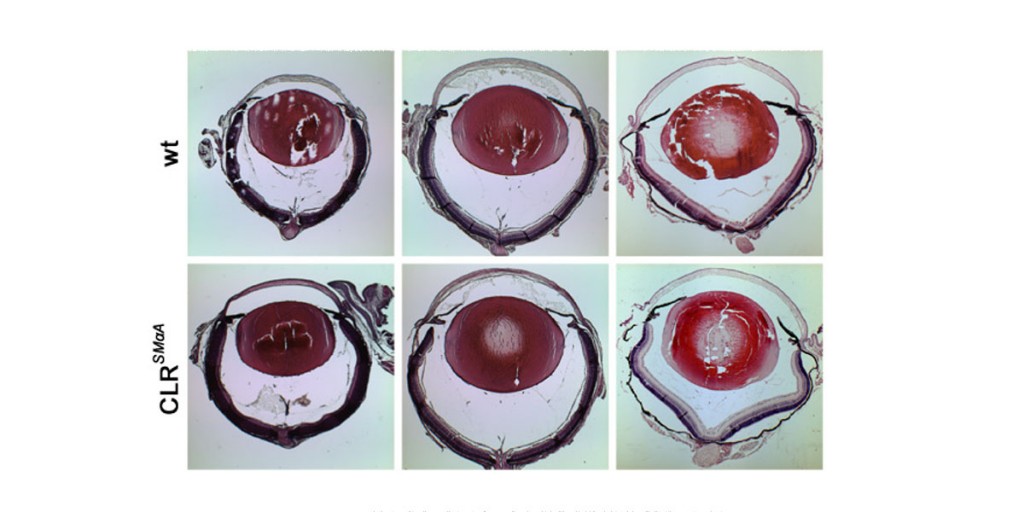

Generation of a new animal model for human acute angle-closure glaucoma. Read here.

Generation of a new animal model for human acute angle-closure glaucoma. Read here.